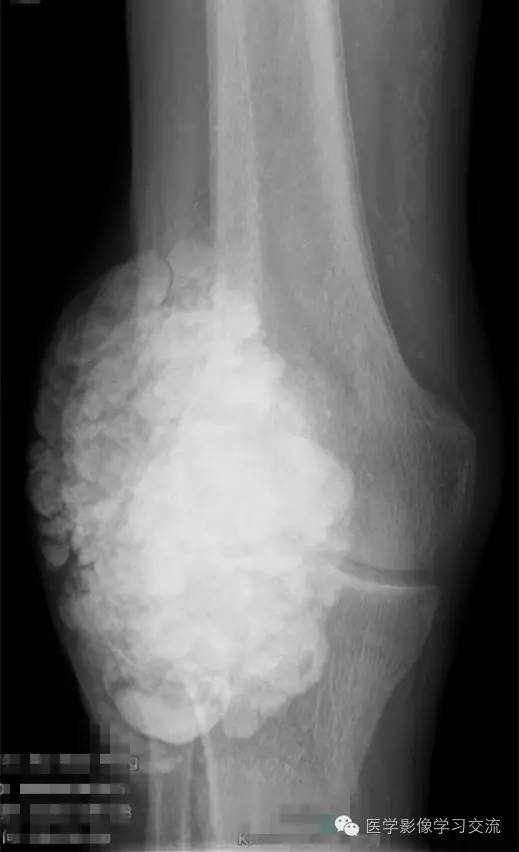

X线检查如下:

X 线检查是诊断 TC 的基本方法,其表现为关节旁关节伸侧软组织中,呈大小不一的钙化结节集结而成的分叶状团块,呈“卵石样” ,范围较广者可呈“流注状” ; 病变一般不累及邻近关节或骨骼。

CT 与X 线平片表现一致,但CT 对病变部位、形态及范围的显示更为全面,能清楚显示病变与邻近关节及骨骼的关系。